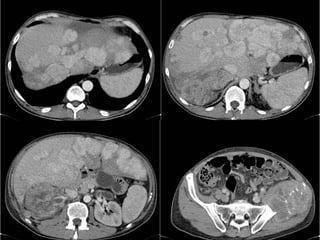

Estudio de Elección:   TC Trifásica Renal  Sin contraste, contraste en fs. arterial, portal y tardía Informa: Comportamiento, tamaño, extensión, número, calcificaciones. Etapificación : compromiso suprarrenal extensión directa a órganos adyacentes adenopatías retroperitoneales invasión de la vena renal y VCI metástasis a distancia (hígado, huesos, cerebro)